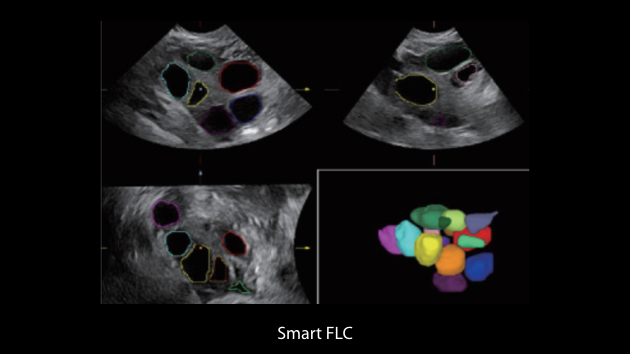

De Nuewa I9, speciaal ontworpen voor vrouwen en neonatale gezondheidszorg, biedt een innovatieve ervaring van binnenuit. Deze innovaties zijn ontwikkeld op basis van diepgaande inzichten in complexe klinische scenario's en bieden nauwkeurige en tijdige antwoorden, evenals een uitstekende effici?ntie en opmerkelijke gebruikerservaring.